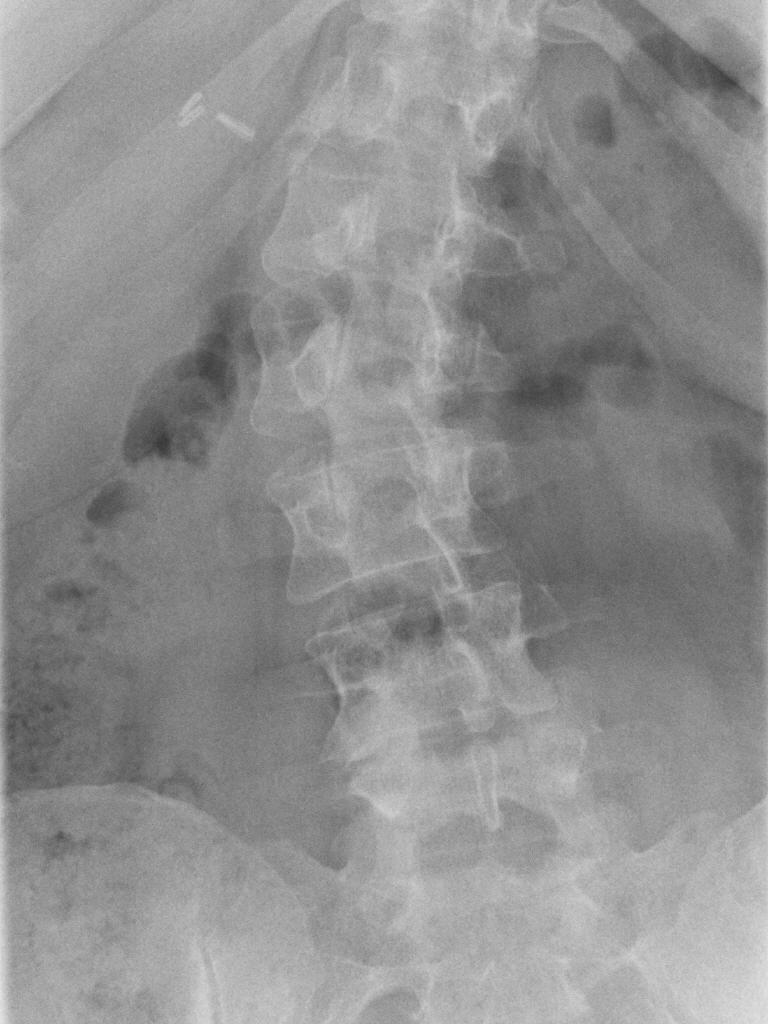

- Aufnahmen der Bauchregion und der Körperweichteile